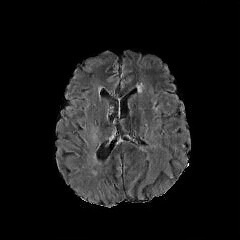

Refer to caption

(a) Normal Brain

(b) Normal Brain

(c) Brain Tumor

(d) Brain Tumor

(e) Normal Liver

(f) Normal Liver

(g) Liver Tumor

(h) Liver Tumor

Figure 4: We show some example brain MRI slices from BratS18 (first row) and Liver CT slices from LiTS (second row). Both normal- and abnormal-looking images are provided.

Aside from the difference in imaging tissue and modality of these two data sets, the tumor regions on the CT images are of different shape and size, as can be seen in Figure 4. Also, many CT scans are acquired in a way that introduces greater noise-like artifacts than MRI. For each dataset, 80%percent8080\% of randomly selected data are used for training and the resting 20%percent2020\% for testing.